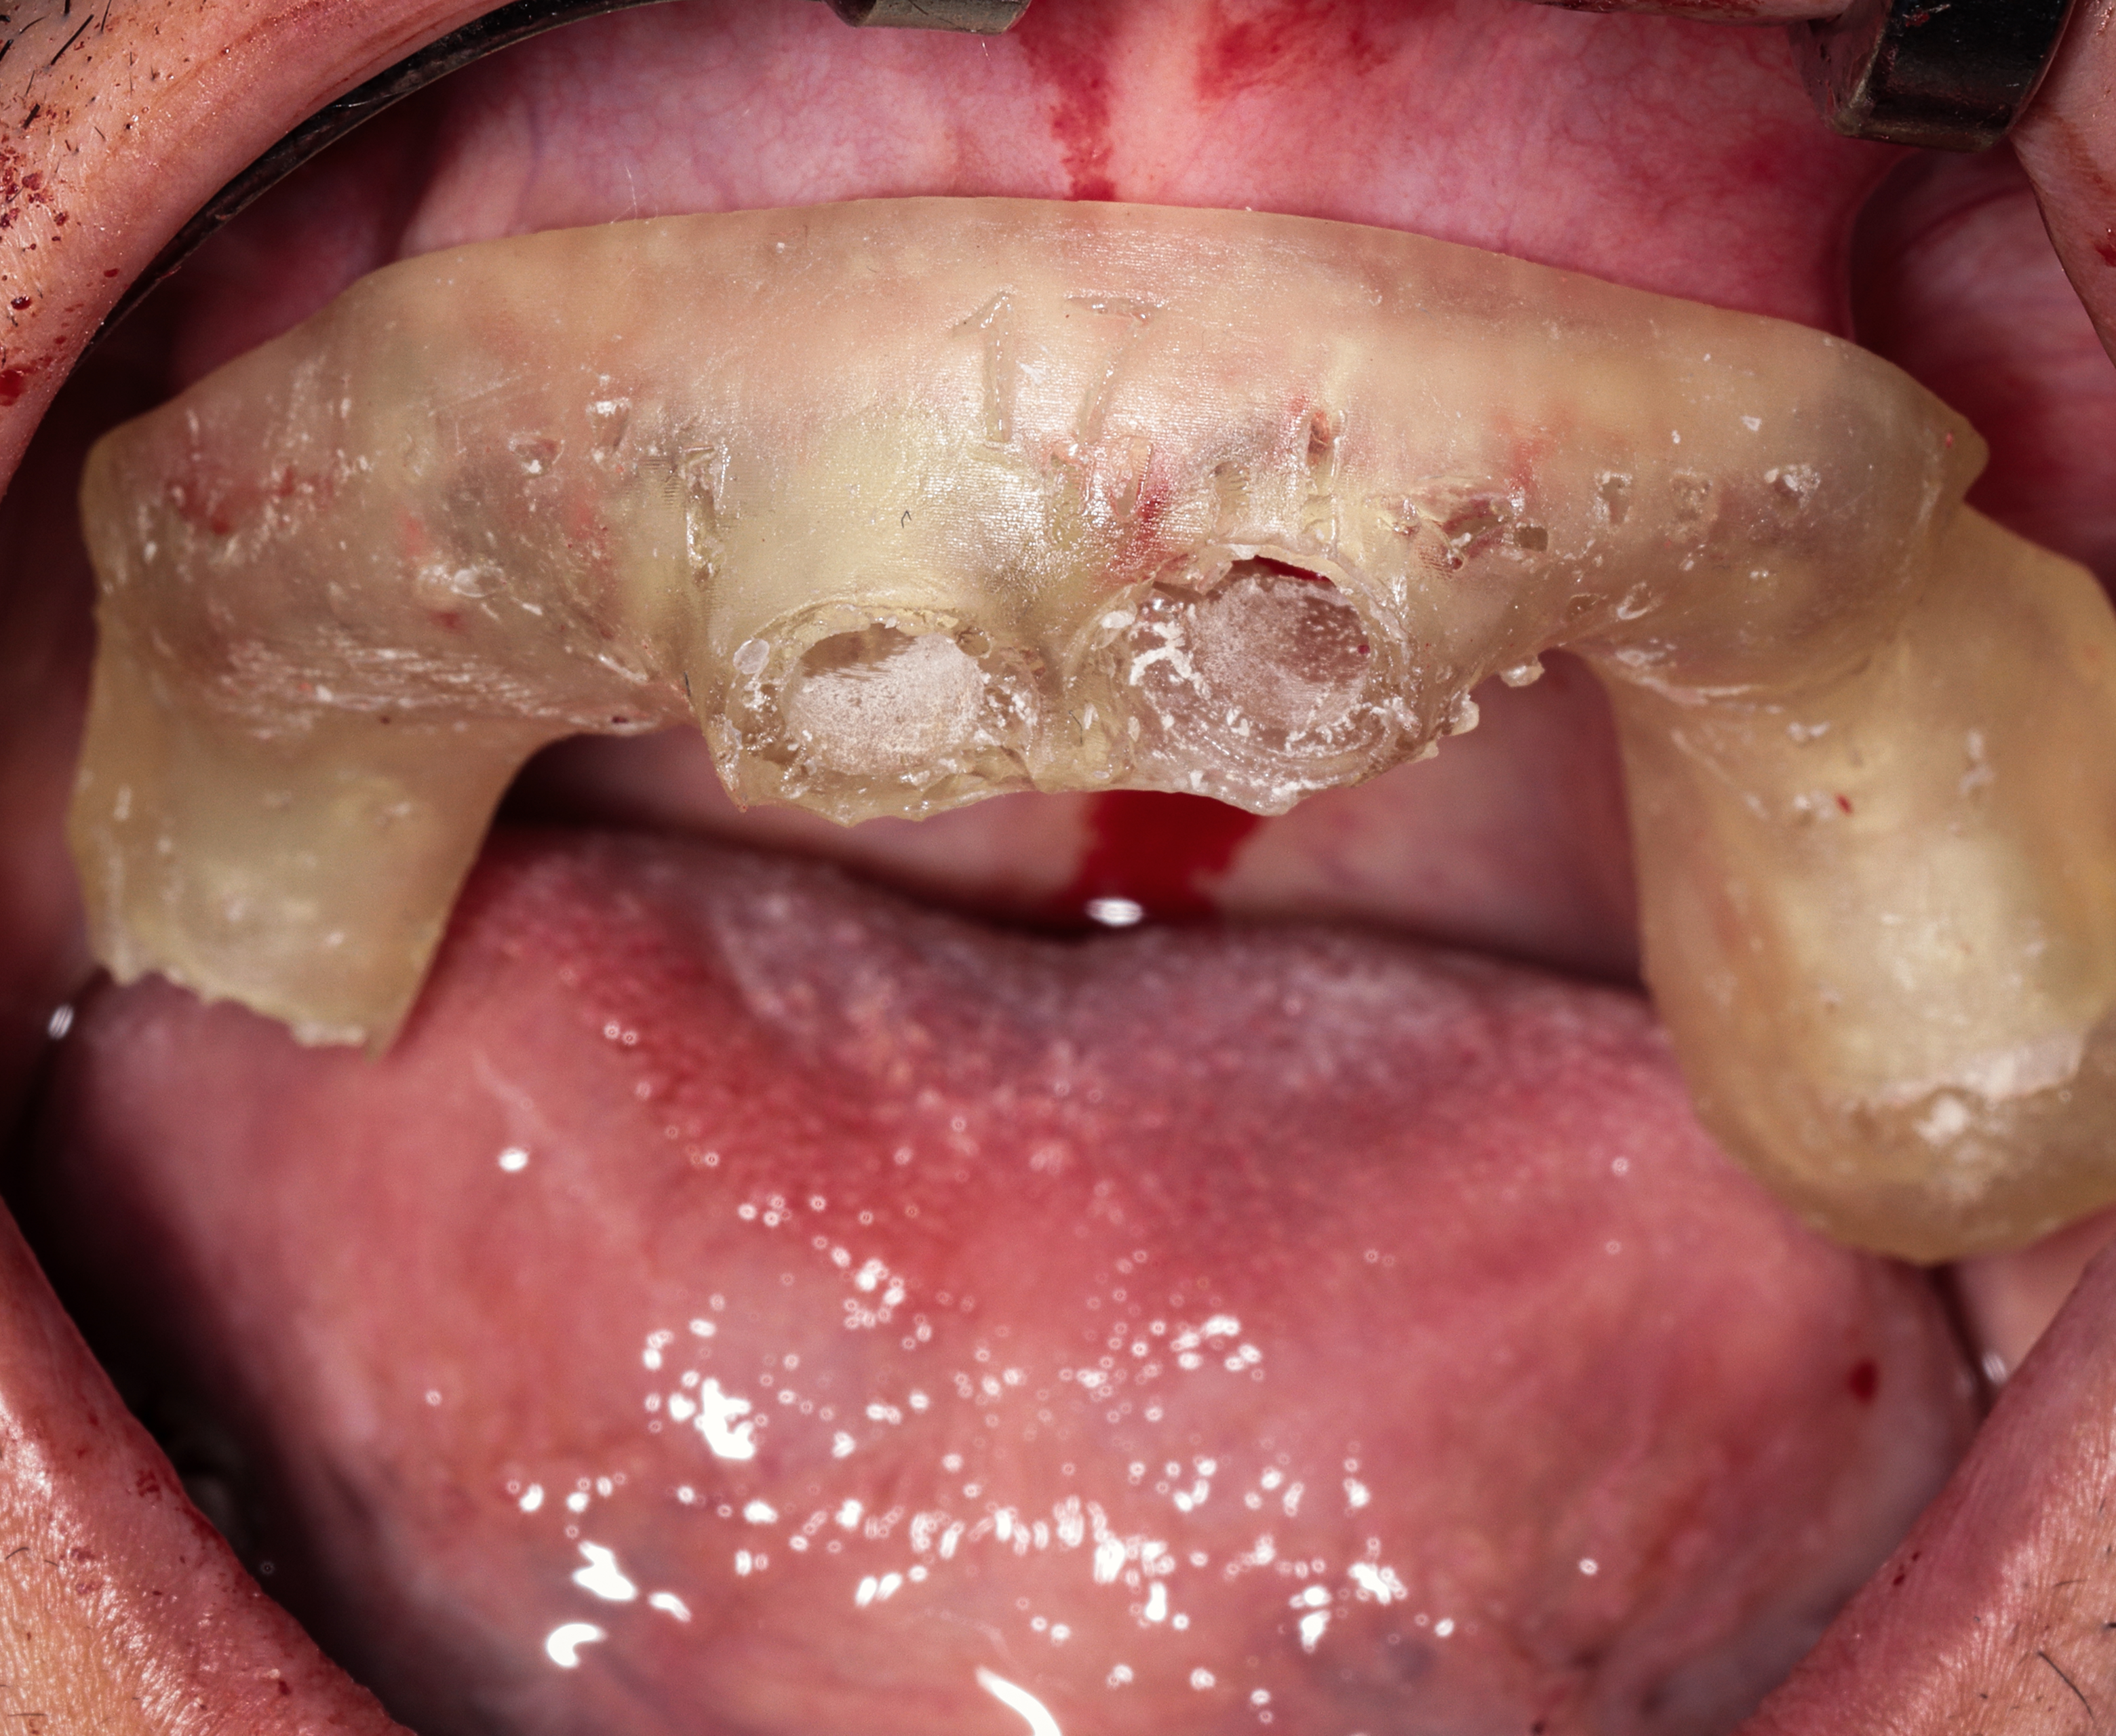

Step 4 — Immediate Temporary Restoration

- Same-day delivery of a full set of temporary fixed teeth

- Instant improvement in Jonathan’s smile, speech, chewing function, and facial proportions